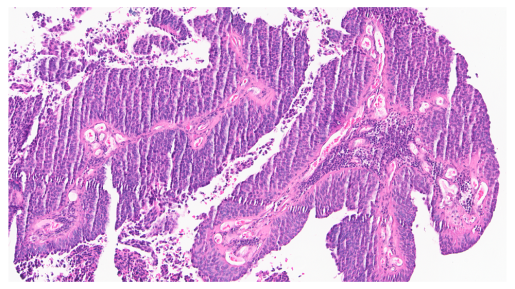

About one quarter of patients with muscle-invasive bladder cancer (MIBC) may be treated and derive a benefit with the current standard chemotherapy, while many others do not respond to available treatments. To better understand why some tumors resist chemotherapy and identify better ways to treat those cancers, researchers at Baylor College of Medicine have conducted a detailed molecular analysis of MIBC tumors. The results, published in Cell Reports Medicine, offer potential new ways to identify which patients will benefit from chemotherapy and reveal possible new treatment strategies.

The researchers studied 60 MIBC tumor samples using a comprehensive multi-omics approach which included genomics (sequencing the genes of the tumor), transcriptomics (analyzing which genes are turned on or off), proteomics (the proteins produced by the tumor) and phosphoproteins (proteins with chemical tags that control their activity).